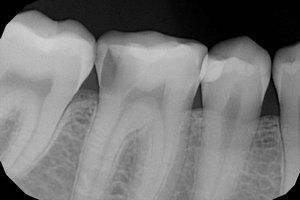

Болит верхний передний зуб при каком либо давлении/нажатии на него. Я подозреваю, что это пульпит. Но до этого несколько ночей провел на холоде. Зуб заболел два дня назад (то есть вчера). Я пришел с работы, лег спать и боль прошла. Сегодня после смены то же самое.

Подскажите, правильно ли я подозреваю болезнь и во сколько может обойтись примерно лечение?

Скорее всего, это периодонтит. Лечение проходит в несколько посещений и обойдётся Вам, согласно нашему прейскуранту, в около 7000 рублей.